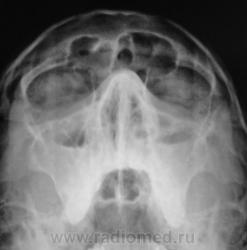

Пол пациента: Мужской пол Тип патологии: Воспалительное заболевание неинфекционной природы Область исследования: Челюстно-лицевая область и шея Методы исследования: Rg Пациент направлен в рентгеновский кабинет отоларингологом для рентгенографии придаточных полостей носа. https://radiomed.ru/sites/default/files/styles/case_slider_image/public/user/12/2.p8200013a.jpg?itok=jgcLkk45 https://radiomed.ru/sites/default/files/styles/case_slider_image/public/user/12/3.p8200014.jpg?itok=Pr-IFQNU https://radiomed.ru/sites/default/files/styles/case_slider_image/public/user/12/4.p8200014a.jpg?itok=rq9pzey- ID:5735 Пнд, 23/08/2010 - 21:49 #1 Глазков Игорь А... Не на сайте Был на сайте: 9 месяцев 1 неделя назад Зарегистрирован: 19.12.2008 - 20:41 Публикации: 1597 экссудат гайморит. правосторонний фронтит, тоже с экссудатом Прийди к Себе Пнд, 23/08/2010 - 23:02 #2 Шаба Не на сайте Был на сайте: 3 года 4 месяцев назад Зарегистрирован: 19.08.2010 - 22:01 Публикации: 122 двухсторонний гайморит, правосторонний фронтит в фазе эксудации.

экссудат гайморит. правосторонний фронтит, тоже с экссудатом

двухсторонний гайморит, правосторонний фронтит в фазе эксудации.